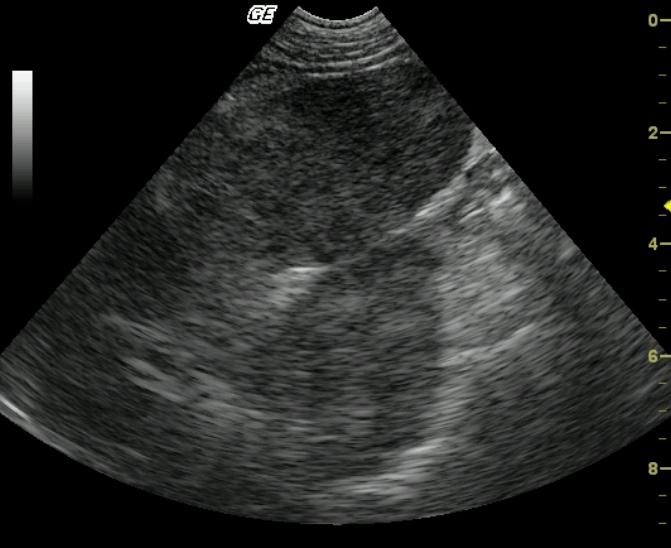

Coarse architecture is noted in both the spleen and liver with irregular capsular contour, echogenic and irregular tissue striations with nodular changes. This universal deviation from parenchymal architecture in both organs suggests a neoplastic process in both liver and spleen. The linear echogenic focus in the near field is a core biopsy needle.

Fibrosarcoma, liver and spleen